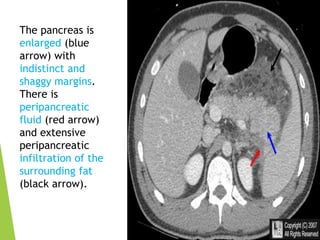

The pancreas is

enlarged (blue

arrow) with

indistinct and

shaggy margins.

There is

peripancreatic

fluid (red arrow)

and extensive

infiltration of the

surrounding fat

(black arrow).

The pancreas is enlarged(blue arrow) with indistinct and shaggy margins. There is peripancreatic fluid (red arrow) and extensive peripancreatic infiltration of the surrounding fat (black arrow).